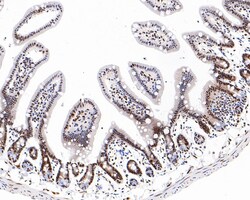

| Immunohistochemistry (Paraffin), Western Blot, Immunocytochemistry | |